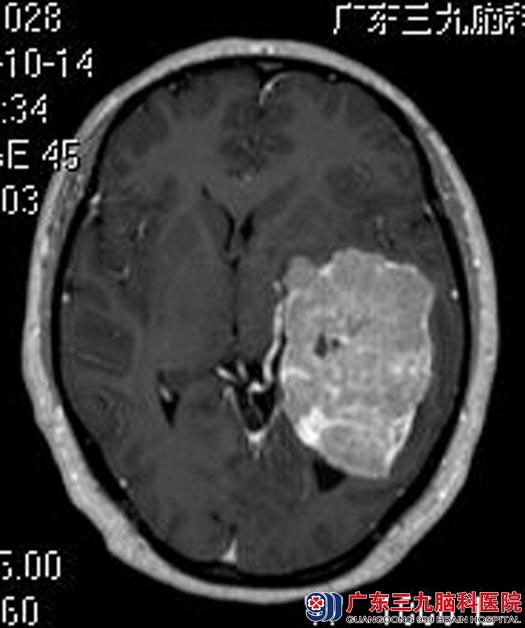

入住广东三九脑科医院综合神经外科,头颅MR检查提示:左侧颞叶区小脑天幕上方示一巨大不规则团块状肿块影,大小约为8.1cm×5.1cm×5.9cm;头颅CTA检查提示肿瘤血供极其丰富,左侧大脑中、后动脉受压移位。

脑膜瘤是颅内常见的良性肿瘤,对药物和放射治疗均不敏感,手术切除是可供选择的方法。完善相关检查后,由鲁明主任主刀,在全麻下行左侧小脑幕山巨大脑膜瘤切除术,术中显微镜下见淡红色肿瘤组织,质韧,血供丰富,予电磁刀全切肿瘤。术后,朱女士恢复很好,已康复出院。术后病理结果:脑膜瘤。